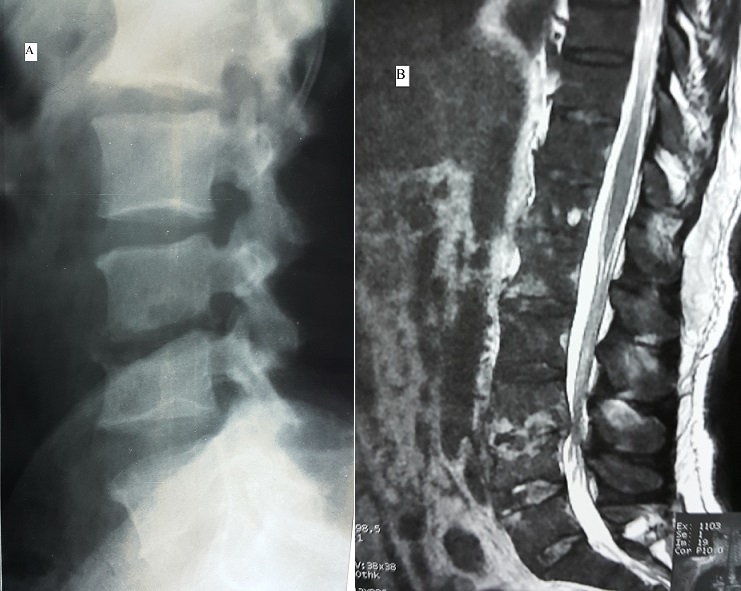

Il s’agit d’un patient de 47 ans, ayant comme antécédent une ponction biopsie prostatique il ya 3 mois. Le patient consulte pour des douleurs du bas du dos d’aggravation rapidement progressive avec apparition depuis une semaine des lombosciatalgies bilatérales mal systématisées. L’examen clinique trouve un patient apyrétique, sans déficit sensitivomoteur ni troubles sphinctériens. L’examen du rachis trouve uns syndrome rachidien lombaire en regard de L3-L4et L5. La radiographie du rachis lombaire a montré un pincement discal en L3-L4 avec érosion des plateaux vertébraux adjacents (A). L’IRM a objectivé la spondylodiscite L3-L4 (B). Une ponction biopsie discale a posé le diagnostic de spondylodiscite mycosique à candida albicans. Les investigations paracliniques n’ont pas objectivé d’immunodépression. Le patient a été mis sous traitement antimycosique avec contention par corset ; l’évolution clinique et biologique était favorable. Les spondylodiscites mycosiques sont rares (1 à 2% des spondylodiscites infectieuses) et sont l’apanage des sujets immunodéprimés, sous traitement antibiotique prolongé ou ayant un cathéter d’alimentation parentéral.